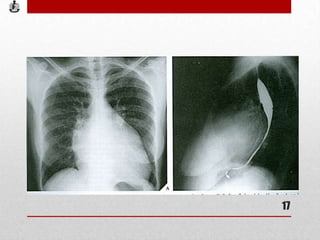

• Rx AP de tórax

usualmente muestra silueta cardiaca de

tamaño normal y un perfil izquierdo con

cuatro arcos que corresponden de arriba

abajo a:

aorta

pulmonar abombada,

orejuela izquierda prominente

ventrículo izquierdo .

Cuando existe hipertensión pulmonar

importante, se observa dilatación del

cono pulmonar (segundo arco del borde

izquierdo de la silueta) y de las ramas, así

como dilatación de ambas cámaras

derechas más o menos importante.